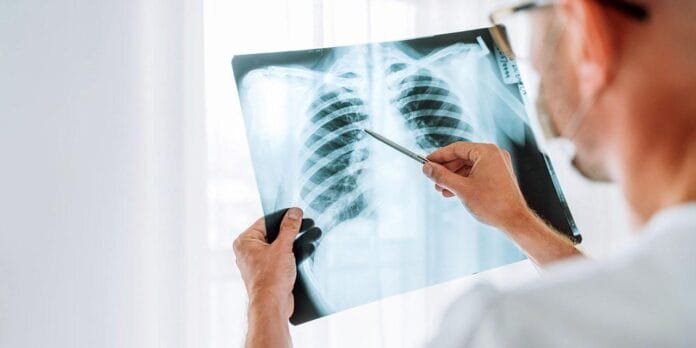

PIEDRAS NEGRAS, COAH.- Actualmente, 29 casos de tuberculosis están siendo atendidos en los seis Centros de Salud de la Jurisdicción Sanitaria Uno de Piedras Negras, informó Priscila Hernández López, coordinadora de Prevención y Promoción de la Salud.

Explicó que los médicos de estos centros identifican a pacientes con síntomas pulmonares sospechosos y los refieren al Centro de Micobacteriosis, donde se les realiza una baciloscopía para confirmar o descartar la enfermedad.

Agregó que durante 2024 se realizaron mil 292 baciloscopías, de las cuales 78 resultaron positivas.